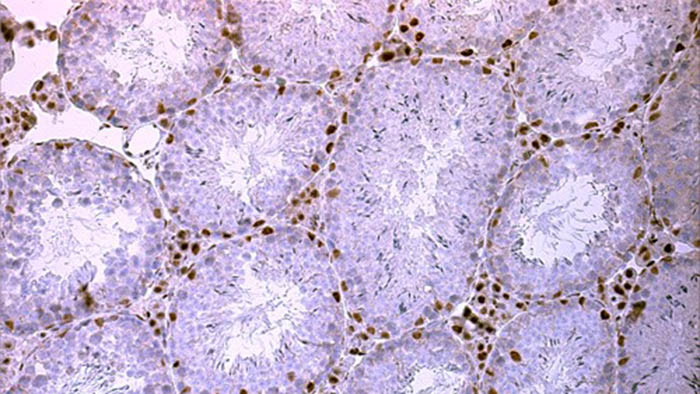

Kudosleikekuva hiiren kiveksestä.